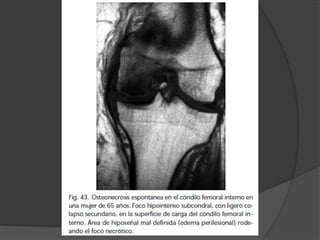

Osteonecrosis

 Se instala cuanto el traumatismo produce daño

vascular

 Causas no traumáticas

 Embolización arterial: Hb-patías, descompresión, embolia

grasa pancreatitis

 Vasculitis : LES

 Presión intraósea elevada

 Inhibición de la angiogenia (esteroides)

 Tensión mecánica

 Exposición a radiación